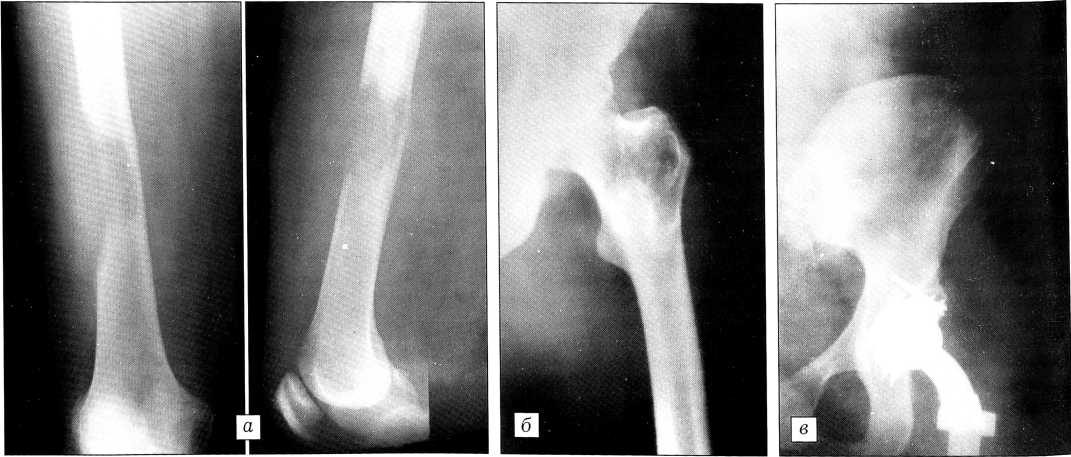

На рентгенограммах (рис. 1) в дистальном метаэпифизе большеберцовой кости определяется очаг остеолитической деструкции 9x5,5 см, переходящий на эпифиз и нижнюю треть диафиза, с мягкотканным компонентом, разрушением коркового слоя по передней и медиальной поверхности и небольшим периостозом типа слоистого. Структура таранной кости и смежных отделов разрежена. Заключение: рентгенологическая картина более соответствует саркоме мягких тканей голеностопного сустава (синовиальная саркома). Нельзя исключить первичную костную опухоль или метастаз.

Рис. 1. Рентгенограммы больного С-ва.

Основной вопрос состоял в том, первична ли костная или мягкотканная опухоль. Принимая во внимание анамнез (вначале появилась опухоль мягких тканей, которая увеличивалась под воздействием физиотерапии), а также выявленные рентгенологические изменения (кость как бы «съедена» этой мягкотканной опухолью), были все основания считать опухоль синовиальной саркомой. При обследовании по органам патологических изменений не обнаружено.